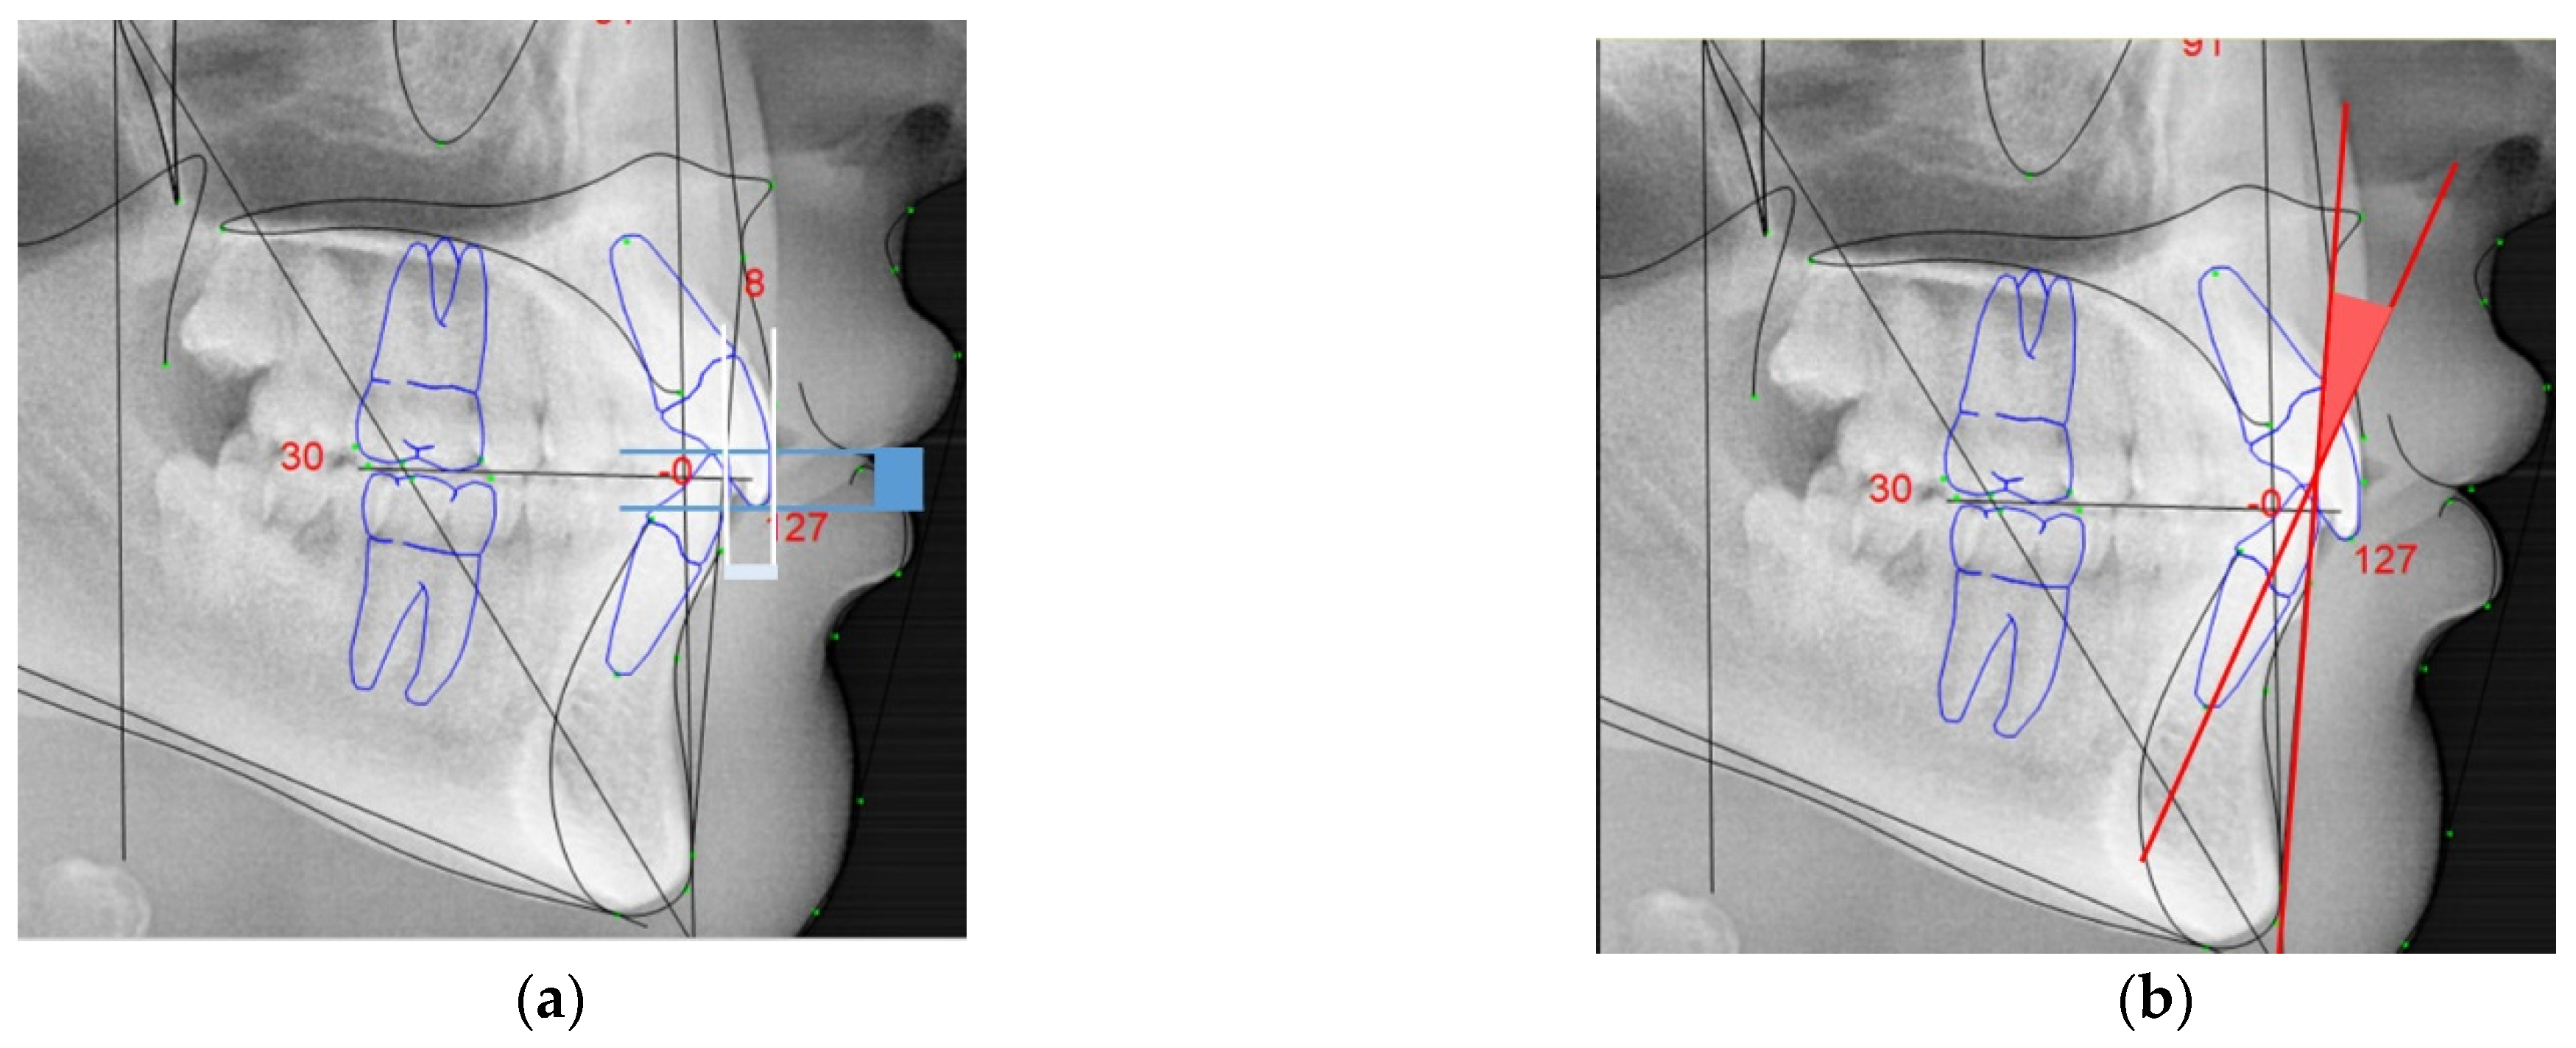

• Overjet: anterior-posterior overlap of the upper incisors over the lower incisors (in white, Figure 3a);

• Overbite: superior–inferior overlap of the upper incisors over the lower incisors measured relative to the incisal ridges (in blue, Figure 3a);

• Lower incisor protrusion: distance between the coronary extremity of the lower incisor to the A/Pog line (in red, Figure 3b).